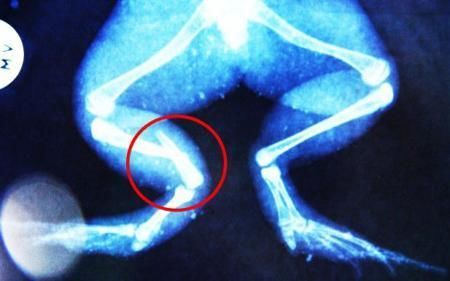

環球網4月2日報道 據《每日郵報》報道,上個月,南非大牛蛙布魯萊的右小腿被鄰居家的一只狗咬到,導致粉碎性骨折,現在經過2個小時的手術,它的斷腿已經被接上,它也因此成為有史以來第一只通過外科手術用鋼針接上斷腿的青蛙。

野生生物專家安妮經常為學校寫教材,她認為這是人類第一次通過手術給一只青蛙接斷腿。在手術開始階段,獸醫把少量給狗用的麻醉藥注入到這只青蛙體內,讓它失去知覺。然后他在布魯萊的斷腿上切開一個小口,把一根小鋼針植入腿里。最后獸醫給它縫了9針,把切口縫合在一起。僅僅幾周后,布魯萊就能在安妮家附近活動了。這只青蛙大約已有25歲,主要以嚙齒動物、蛇和其他青蛙為食。布魯萊所屬的牛蛙種群正在不斷減小,目前只能在非洲南部的濕地里才能看到這種青蛙。